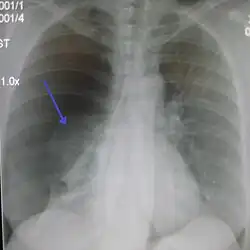

Chest X-ray

A plain chest radiograph, ideally with the X-ray beams being projected from the back (posteroanterior, or "PA"), and during maximal inspiration (holding one's breath), is the most appropriate first investigation.[35] It is not believed that routinely taking images during expiration would confer any benefit.[36] Still, they may be useful in the detection of a pneumothorax when clinical suspicion is high but yet an inspiratory radiograph appears normal.[37] Also, if the PA X-ray does not show a pneumothorax but there is a strong suspicion of one, lateral X-rays (with beams projecting from the side) may be performed, but this is not routine practice.[18][22]

Chest X-ray showing a pneumothorax on the right (left in the image), where the absence of lung markings indicates that there is free air inside the chest -

It is not unusual for the mediastinum (the structure between the lungs that contains the heart, great blood vessels, and large airways) to be shifted away from the affected lung due to the pressure differences. This is not equivalent to a tension pneumothorax, which is determined mainly by the constellation of symptoms, hypoxia, and shock.[16]

The size of the pneumothorax (i.e. the volume of air in the pleural space) can be determined with a reasonable degree of accuracy by measuring the distance between the chest wall and the lung. This is relevant to treatment, as smaller pneumothoraces may be managed differently. An air rim of 2 cm means that the pneumothorax occupies about 50% of the hemithorax.[18] British professional guidelines have traditionally stated that the measurement should be performed at the level of the hilum (where blood vessels and airways enter the lung) with 2 cm as the cutoff,[18] while American guidelines state that the measurement should be done at the apex (top) of the lung with 3 cm differentiating between a "small" and a "large" pneumothorax.[38] The latter method may overestimate the size of a pneumothorax if it is located mainly at the apex, which is a common occurrence.[18] The various methods correlate poorly but are the best easily available ways of estimating pneumothorax size.[18][22] CT scanning (see below) can provide a more accurate determination of the size of the pneumothorax, but its routine use in this setting is not recommended.[38]

Not all pneumothoraces are uniform; some only form a pocket of air in a particular place in the chest.[18] Small amounts of fluid may be noted on the chest X-ray (hydropneumothorax); this may be blood (hemopneumothorax).[16] In some cases, the only significant abnormality may be the "deep sulcus sign", in which the normally small space between the chest wall and the diaphragm appears enlarged due to the abnormal presence of fluid.[19]